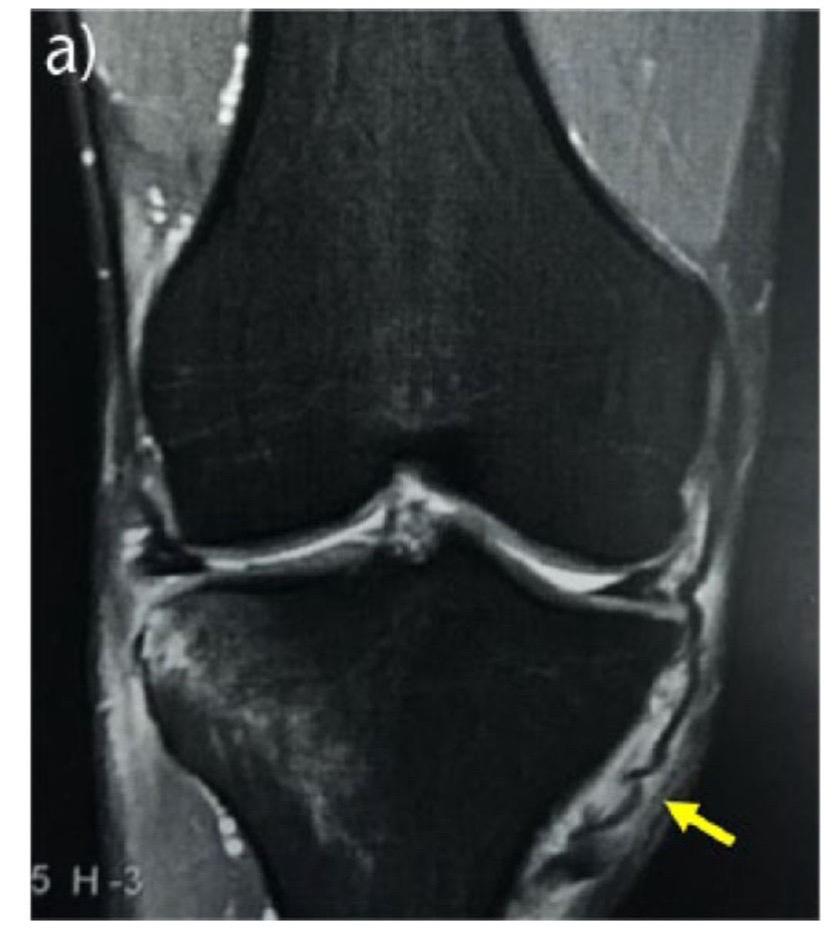

看懂【内侧副韧带】内侧副韧带,膝关节内侧稳定的核心。抵抗膝关节外翻应力,限制胫骨外旋。